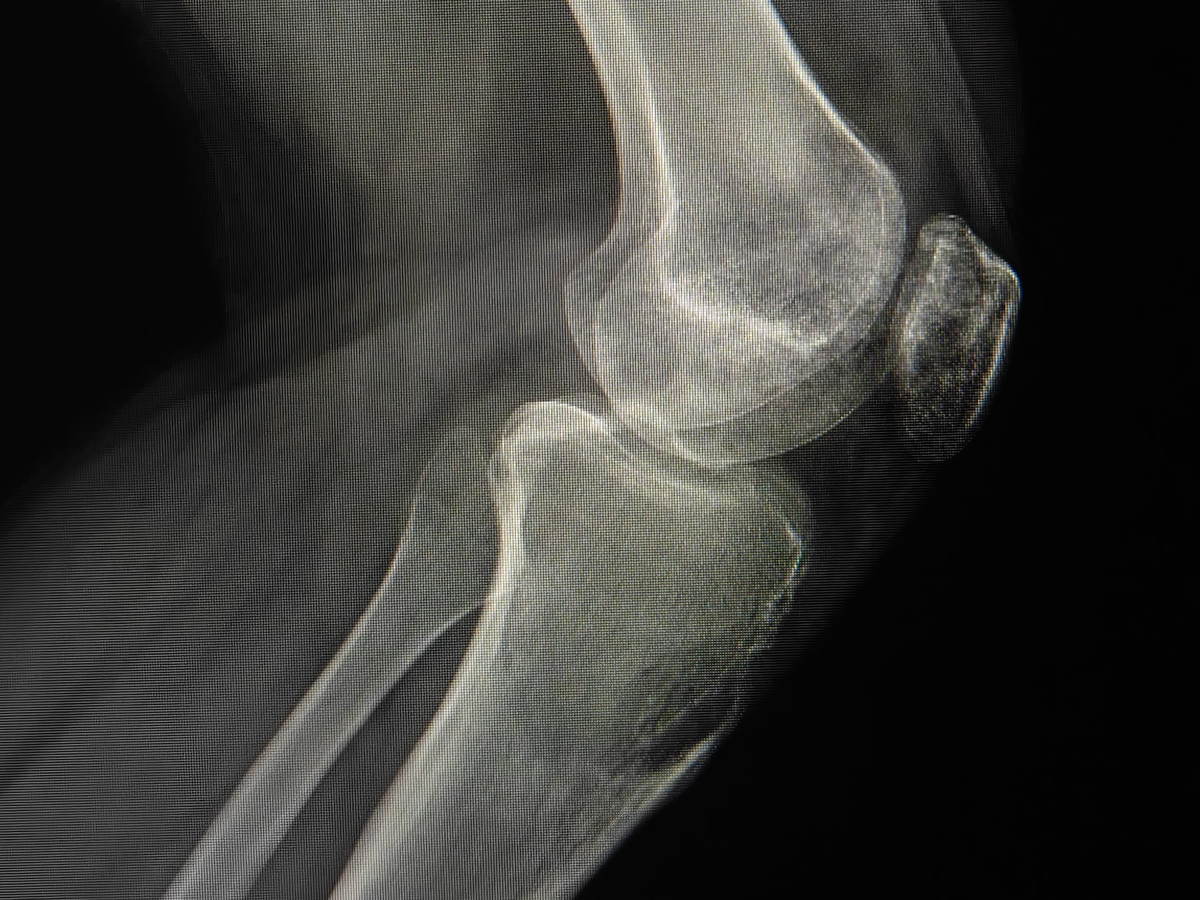

Estoy recaudando fondos para mi novio, quien actualmente tiene un tumor agresivo en la rodilla (tibia). En este momento estamos en espera de los resultados de su biopsia para conocer exactamente el diagnóstico y el tratamiento que seguirá.